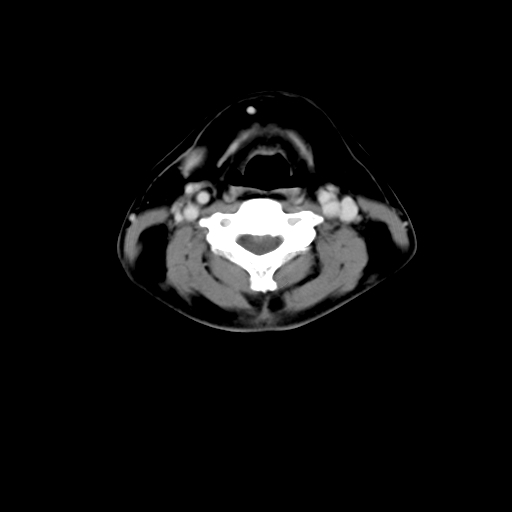

标题: CT24019:男,45岁,发现颈部肿物5个月。 [打印本页]

男,45岁,发现颈部肿物5个月,彩超示:双侧颈部及下颌部软组织增厚。

考虑双侧颈项部良性对称性脂肪增多症。

双侧颈项部脂肪沉积